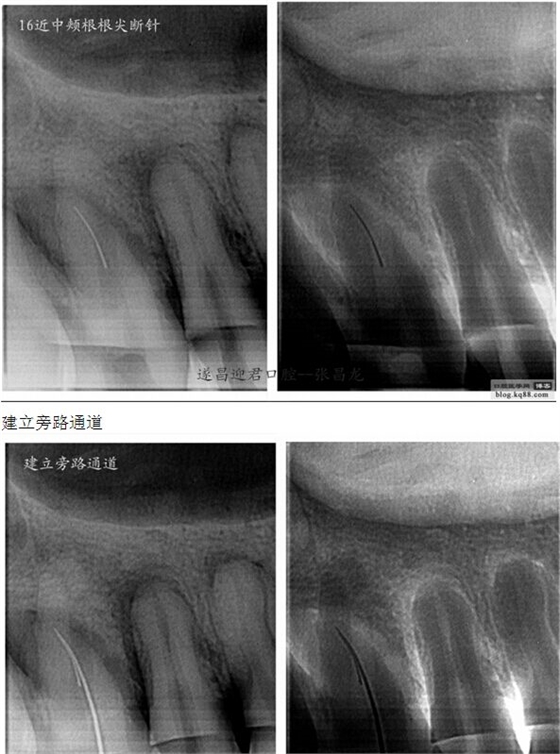

下面是我最近的一個患者,患者14,15,16均因楔狀缺損導(dǎo)致牙髓壞死,根管治療期間,16的近中頰根發(fā)生了斷針。